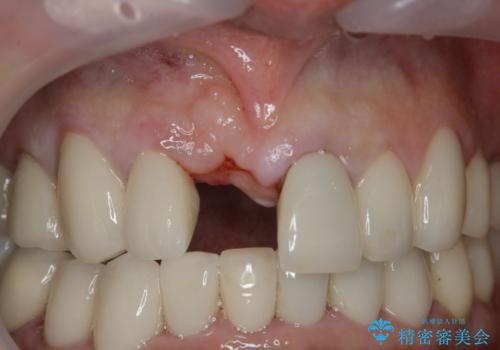

- 事故による外傷で前歯に歯根が真っ二つに折れてしまい、保存不可能となってしまった部分にインプラント治療を計画しました。

患者様のご要望もあり、審美性の確保ができる抜歯早期埋入→埋入後即時荷重という手術法を取りました。

近年、インプラントの素材や手術法の研究が進み、保存不可能となった歯牙に対して抜歯してすぐインプラントを埋入し、さらに直後から仮歯がを入れ噛むことができる【抜歯即時埋入】【即時荷重】という技法が確立されました。

従来、前歯部分のインプラントでは周囲に残っている自身の歯に仮歯を張り付けることで審美性を保ってきましたが、脱離を繰り返したり食事に耐える強度を保つのが難しいという側面がありました。